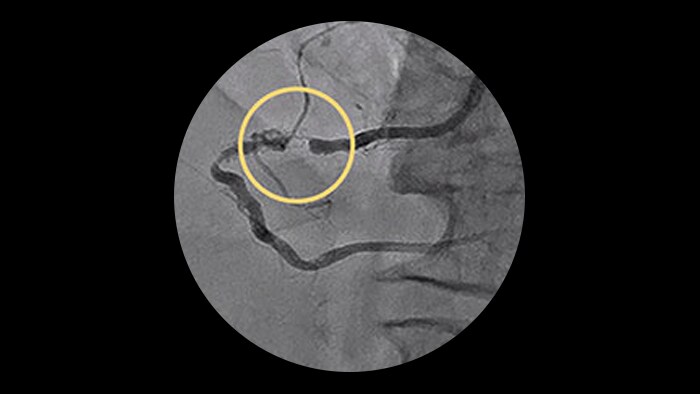

– Diffuse CAD may be underestimated by evaluation with coronary angiography.

– Determining reference vessel sizing can be challenging when the vessel is diffusely diseased.